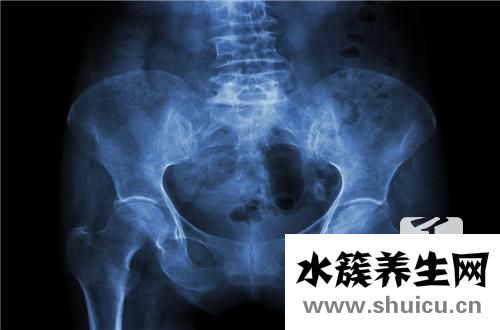

如今,做好分娩后骨盆底肌肉的修復很重要,但是大多數(shù)人認為這種修復工作沒有目的,也沒有必要進行。 實際上分娩后修復骨盆底肌肉非常重要。 如果立即不被維修,則部分韌帶將松動,從而給不必帶來不便。 ...